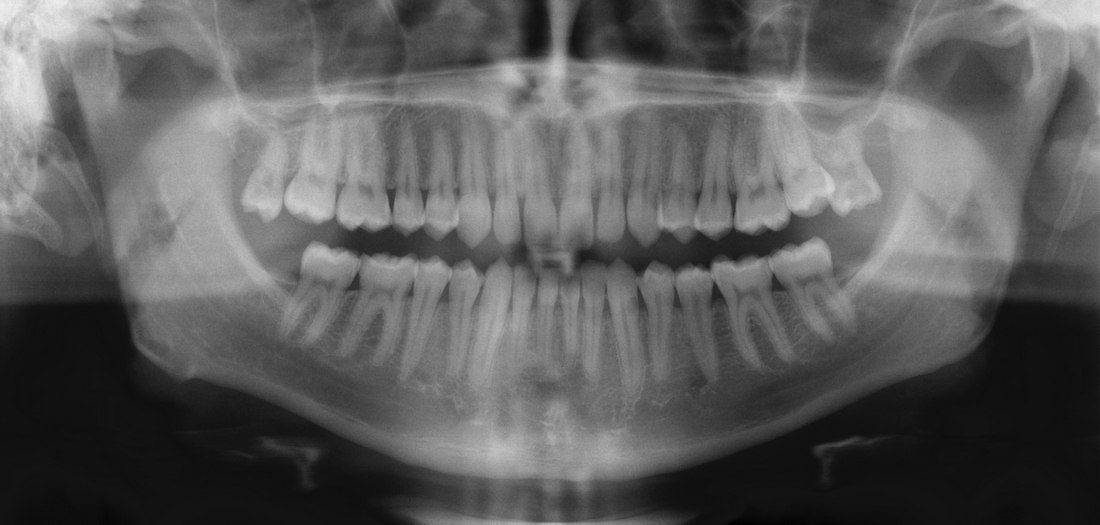

Аноним Срд 07 Май 2014 19:57:02  #1 №67737588

1399478222640.jpg

Привет Двощ. Только что откололся передний зуб, прямо как на пике, прогнил изнутри и воняет, сука. У кого так было, что надо делать? И сколько будет стоить вот это вот все? инфибо вставь орбит на место дырки и так ходи

Аноним Срд 07 Май 2014 20:12:43  #14 №67738525

1399479163870.jpg

Если ты в ДС:

Чистка и экстракция частей зуба - около 10к

Имплантация металла от 30к

Коронка на имплант - 15-20к

кстати, вам совет мучайтесь дальше.

Аноним Срд 07 Май 2014 20:27:36  #29 №67739414

>>67739130

Хуй знает, с рождения такие, скорее наследственность.

Аноним Срд 07 Май 2014 20:29:07  #30 №67739520

>>67739227

Не дс, 400к мухосранск

>>67739362

Нерв 7 лет назад удалили

Аноним Срд 07 Май 2014 20:29:19  #31 №67739537

1399480159204.jpg

>>67737588

А мне прооперировали свищ недавно. Не дорого. Просто фоточку решила прикрепить. Повыебываться. Сейчас там тонюсенькая полоска после операционного шрама.

Аноним Срд 07 Май 2014 20:29:35  #32 №67739552